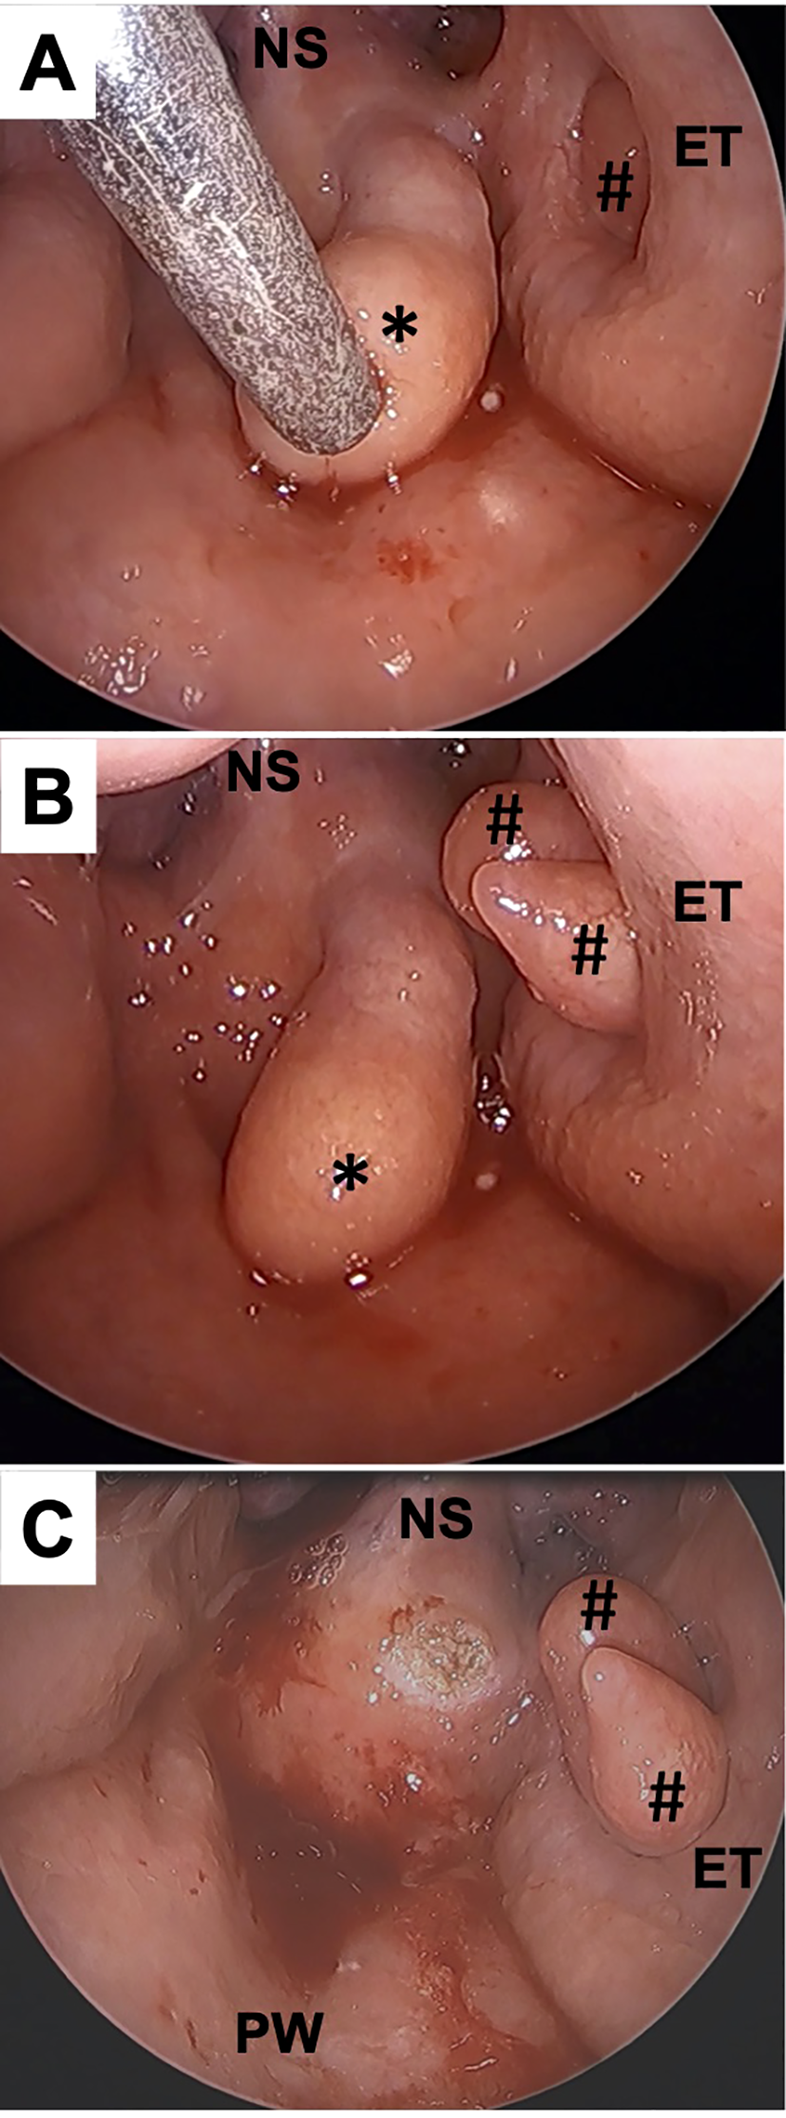

Intraoperative biopsy was performed under general anesthesia with a muscle relaxant for a definitive diagnosis. The base of one of the tumors was shown on the left side of the superior wall of the nasopharynx and was moving back and forth. The other, located in the left pharyngeal orifice of the Eustachian tube, was moving in and out of the Eustachian tube (Figures 2A, B) (Supplementary Video 2). The tumor located on the superior wall was resected at the base by a coblator set at power level 7 for ablation mode (Smith & Nephew Japan, Tokyo, Japan) (Figure 2C). The tumor located in the Eustachian tube appeared to be either a single lobulated mass or multiple masses. Importantly, to avoid permanent disorder of Eustachian tube function, we decided in this case to preserve the tumor in the Eustachian tube.

Figure 2

Intraoperative findings. A 70° rigid endoscope was trans-orally inserted to the oropharynx. Multiple tumors were observed in the nasopharynx. The tumor in the Eustachian tube showed spontaneous contraction (A) and relaxation (B). The tumor arising from the superior wall (*) was resected with a coblator without bleeding (C). #, the tumors in Eustachian tube; NS, nasal septum; ET, Eustachian tube; PW, posterior wall of the nasopharynx.